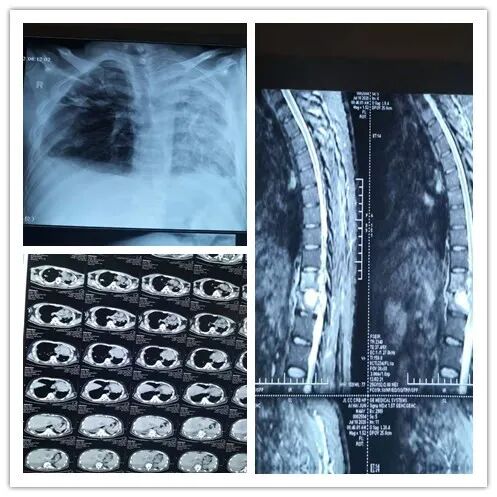

骨科董亚军团队接待了艾先生,看着慕名而来,满怀希望的艾先生,董亚军主任犯了难,艾先生的病诊断非常明确,胸10、11椎体结核及胸12腰1椎管内结核,由于神经压迫,他的下肢已经全瘫,运动M0,必须尽快手术,将椎管内的肉芽肿取出,清除破坏的椎体、解除组织对脊髓的压迫才能使瘫痪的肢体尽可能恢复功能。如果单纯这一个毛病,对身经百战的董亚军团队来说,不是难事,但是,由于艾先生患肺结核多年,一侧肺结核伴有空洞,另一侧肺已经损毁,失去功能,加之损毁肺导致纵膈气管移位,麻醉难度及风险加大,他的身体是否能承受麻醉的风险与手术的“打击”都是个未知数,更别提术后效果是否理想了。患者病情复杂、身体状态差、手术风险大、董亚军赶紧把情况汇报给了主管业务的副院长孙鹏,孙鹏非常重视,说:“病人的病拖延一天,恢复的难度就会增加,患者如此信任我院,我们更应该全力以赴”。他立即组织多学科会诊,考虑到艾先生的特殊情况,专家组制定了多种手术方案。

10月25日,经过医疗、护理、麻醉、检验等科室的精心准备,艾先生被推进了手术室,团队选择了后路椎管减压、椎弓根入路手术方式。经过4个小时10分钟惊心动魄的手术,完全解除了脊髓压迫,并且彻底清除了结核病理组织,艾先生手术非常成功。术后第二天艾先生足趾即能微动,下肢运动感觉明显好转。术后14天,他的疼痛感觉明显改善,双下肢肌力已经恢复到M1,切口愈合良好。艾先生出院时,家人拉着董亚军主任的手,激动地说,立竿见影,立竿见影啊!太感谢省结核病医院的医护人员了,太感谢骨科团队了,看来我们的选择没有错,我们来九台来对了!